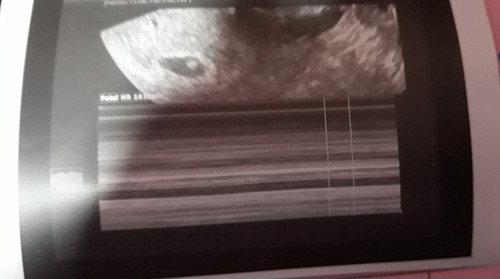

threatening abortion

Hi po mga mommies nkaranas ng Threatening abortion..nkabedrest po ako now ask ko lng po if nawwla n po b ung brown discharge it means po medyo nagiimprove po ung condotion??? Thank you po kc dti mdme po ako bworn discharge ngaun nppnsin q po medyo pawla n po xa... pero maskit prin ung likod q kahihiga ?... godbless po